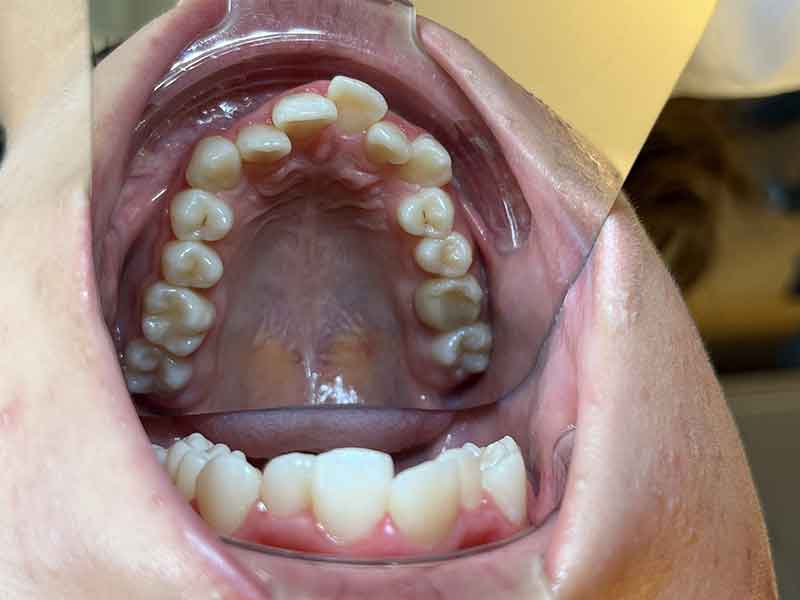

Résultat · Février 2025

En seulement 4 mois de port de la plaque d'expansion, la progression est visible et convaincante.

Le décalage de Classe II est atténué : la relation entre les arcades supérieure et inférieure s'est améliorée

La canine supérieure a commencé à trouver sa place dans l'arcade

L'occlusion latérale est plus harmonieuse

Le maxillaire s'est élargi, avec un effet de chaîne positif sur l'ensemble de la relation entre les deux mâchoires

Le résultat : le maxillaire s'élargit, l'arcade gagne en largeur, les dents disposent de plus d'espace pour s'aligner. Et en corrigeant la largeur de l'arcade supérieure, on améliore mécaniquement la relation entre les deux mâchoires — ce qui réduit directement le décalage de Classe II.